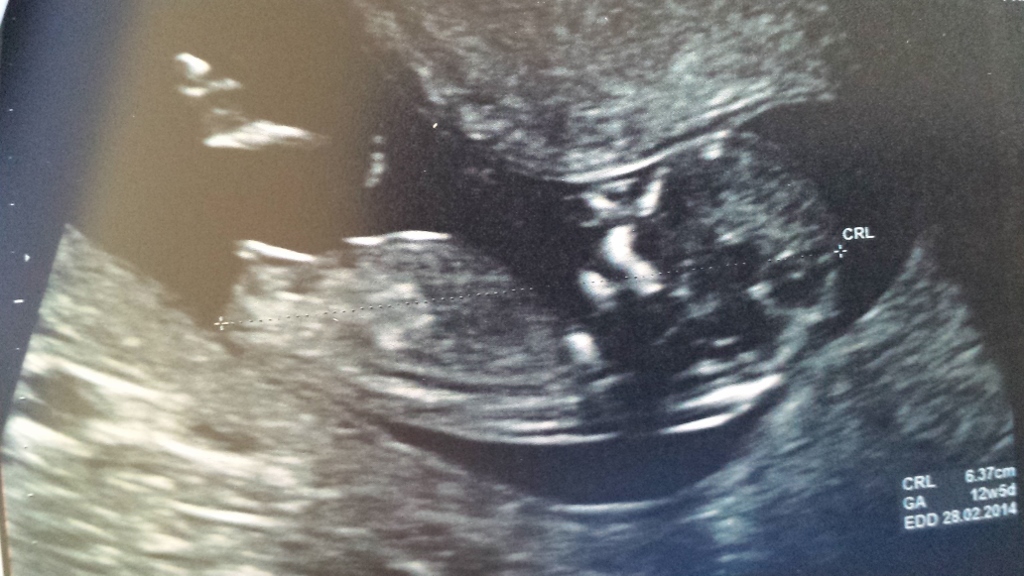

Please guess my nub!! :-)

Attachment 13281Attachment 13282